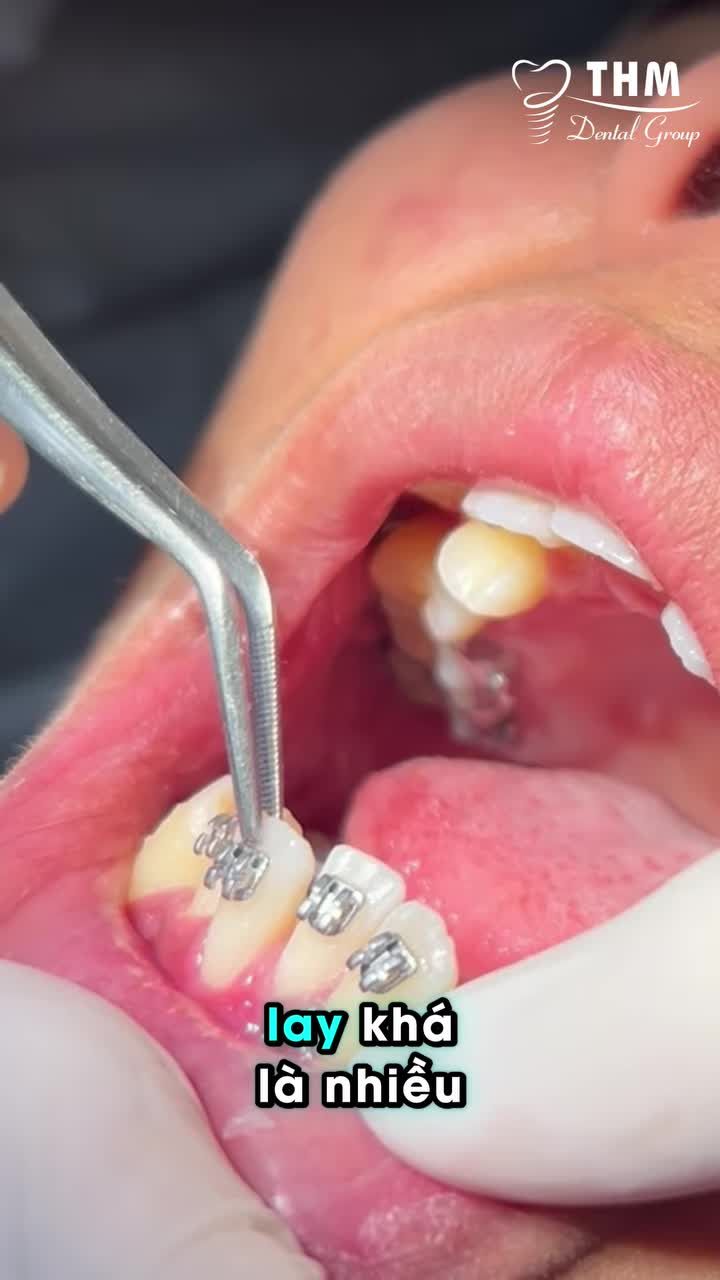

Với những bệnh nhân thuận tiện di chuyển, bác sĩ sẽ chia giai đoạn gắn từng hàm giúp bạn làm quen dần, hạn chế cảm giác ê hay cộm trong những ngày đầu. Dễ dàng ăn uống, sinh hoạt Không kéo dài quá...